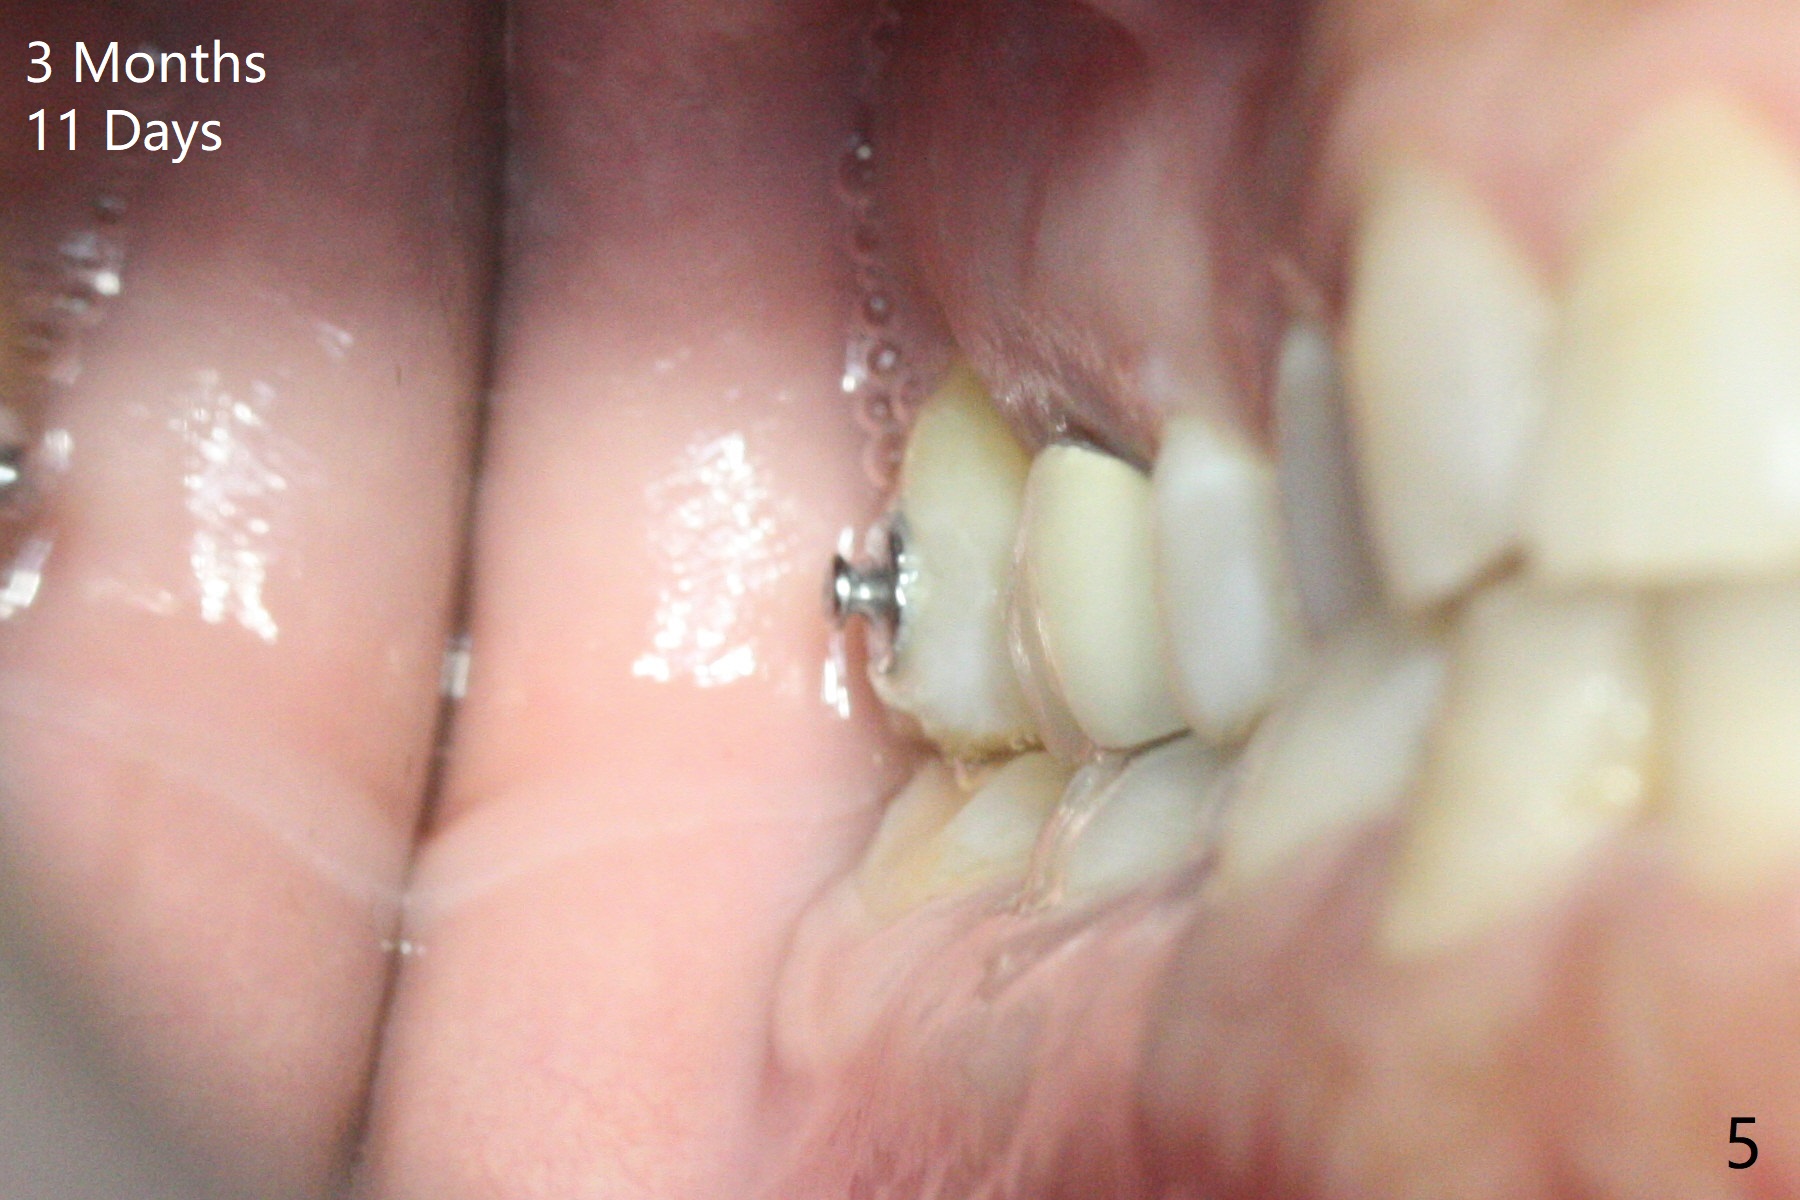

A 51-year-old woman agrees to correct cross bite of R7s 10 years post UR6 crown (Fig.1,2). Composite is placed in LR6 (Fig.3 C) and LL7 for clearance. Lingual buttons are placed in the buccal surface of UR7 (Fig.3 <) and lingual surface of LR7 (Fig.6 ^) with 6 oz. elastic in between. Cross bite correction finishes in 3 months. Photos (Fig.4-6) and PAs (Fig.7,8) are taken 11 days post orthodontic treatment.